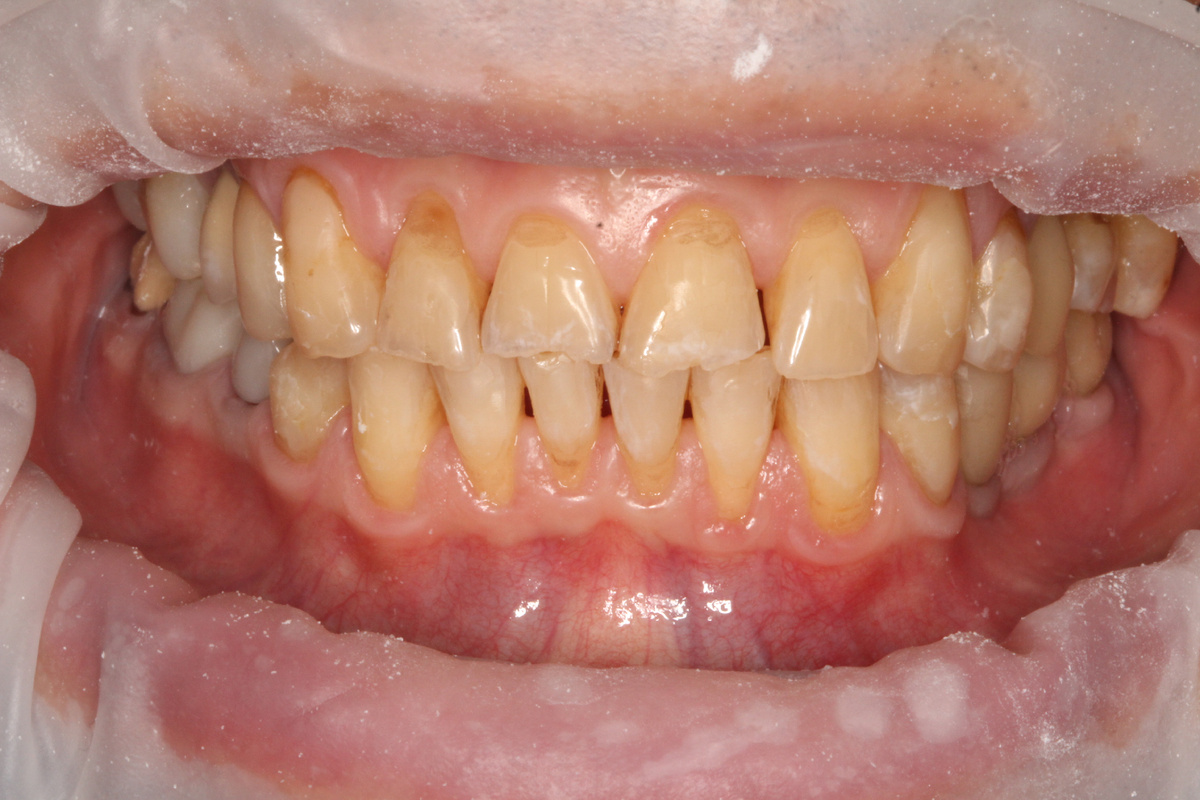

Вместо тысячи слов покажу это фото. Это яркая иллюстрация рецессии десны (у меня таких картинок много, по ходу статьи будут демонстрировать).

Сегодня говорим не только о том, как рецессия возникает, но и почему её нельзя игнорировать.

К сожалению пациент, который пришел сдаваться стоматологу по причине рецессии, - это эксклюзив. Пока ничего не болит, пока есть чем жевать, люди редко тревожатся из-за десён до такой степени, чтобы добровольно записаться на приём. А стоило бы. Но перейдем от докторского брюзжания к фактам и аргументам.